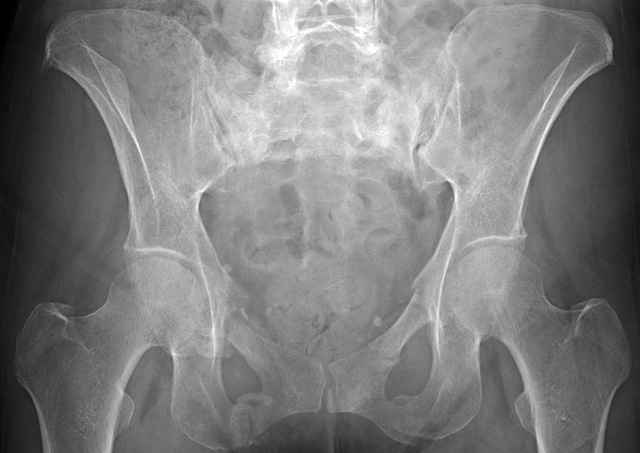

Here are a recent patient’s example slides...

54 yo Female Fell c/o Pain

Initial Films

?Instability on Exam - Limited by Pain

NonOp Initial Mgmt

3 Months After Fall

Continued Pain & Immobility

(+) Instability to Compressive Manual Exam

Pelvic CT Scan - 3 Months After Fall

Sacral Injuries

Ramus Fractures